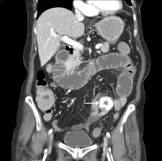

calcified gallstones